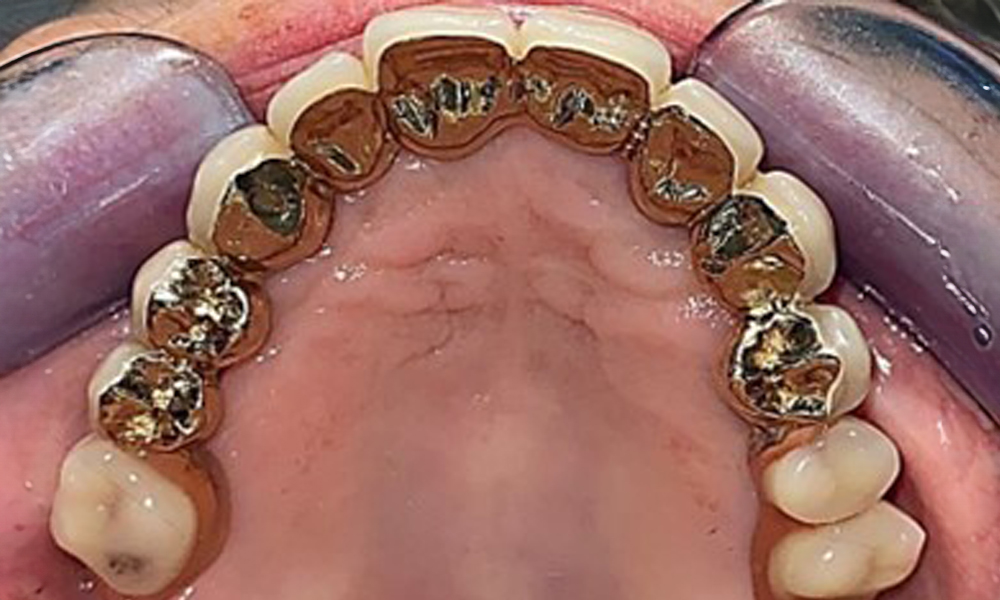

The patient was fitted with a combined removable maxillary telescopic prosthesis more than 25 years ago (Fig. 1, Fig. 2, Fig. 3) and is very happy with her dentures. The patient has an adequate fixed denture for the mandible (Fig. 4).

The dental findings are as follows: Combined removable implant and tooth-supported telescopic prostheses on implants 15, 13, 21, 23, 24, 25 and tooth 11 (Fig. 1, Fig. 2, Fig. 3). The patient was fitted with a fixed mandibular denture. Adequate bridges were present over 37 to 34 and 45 to 47 (Fig. 4), the crown margins were intact and there were no active caries. A composite filling with a marginal gap was present on tooth 43. There was mandibular gingival recession, exposing 1 to 3 mm of root surface. This also applies to 11.

Occlusal view: Maxilla with tooth and implant-supported telescopic prostheses.

Fig. 2: Occlusal view: Maxilla with tooth and implant-supported telescopic prostheses